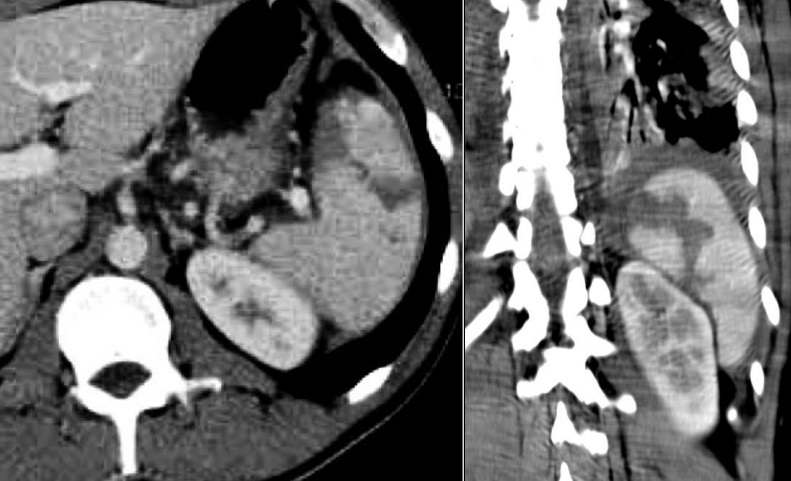

Aspect radiologique TDM d'une

traumatisme et contusion de la rate est image

hypodense lineaire ou en plage de mal limitees .

Image radiologique TDM d'une traumatisme de la rate

en coupe axiale et ẻn coup frontal |

|

Une autre traumatisme /

contusion de la rate est image hypodense en plage un

partie anterieure - interieure de la rate . Image radiologique

TDM en coupe axiale |